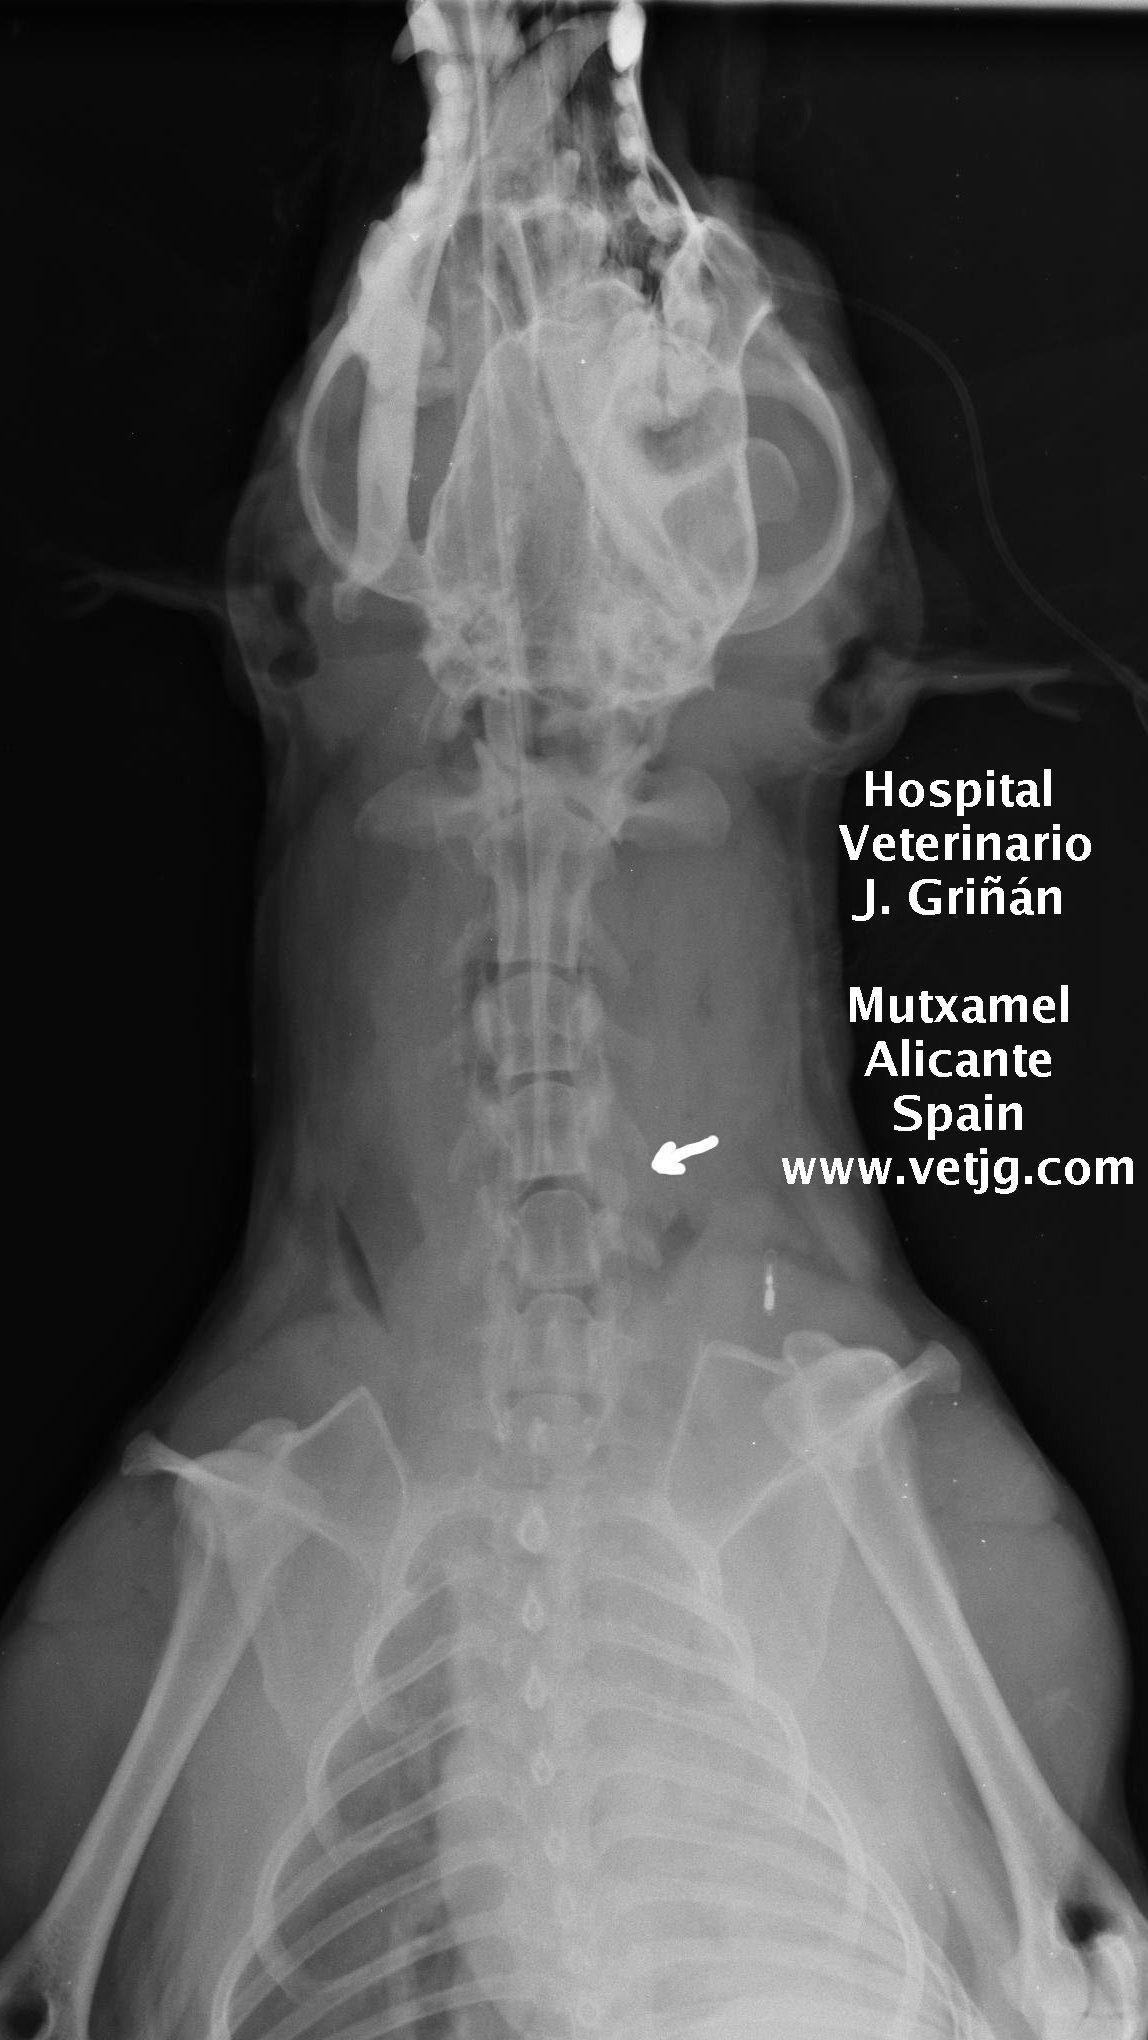

radiografia: imagen del postoperatorio, indicando la zona abordada |